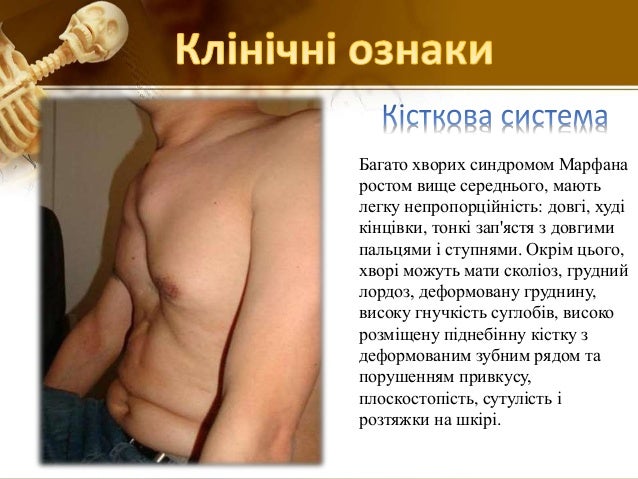

Sindrom marfana tema nauchnoj stati po klinicheskoj medicine chitajte besplatno tekst nauchno issledovatelskoj raboty v elektronnoj biblioteke kiberleninka (Тип файлу jpg)

Sindrom Marfana Tema Nauchnoj Stati Po Klinicheskoj Medicine Chitajte Besplatno Tekst Nauchno Issledovatelskoj Raboty V Elektronnoj Biblioteke Kiberleninka